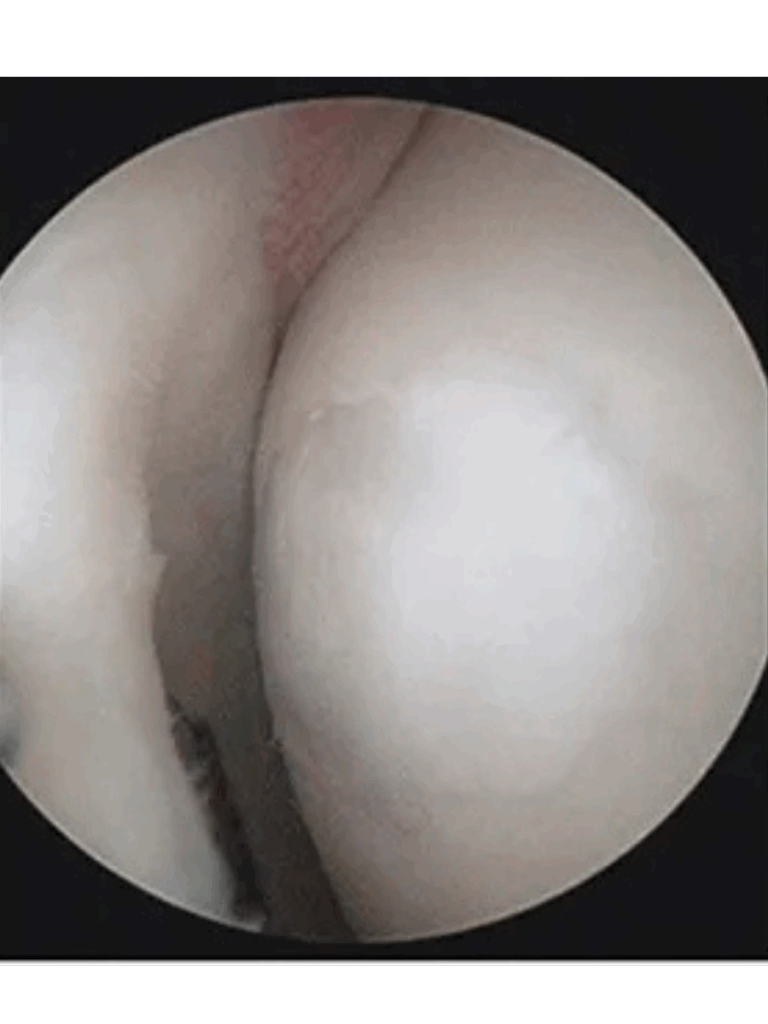

Before Stem Cell Treatment

You can see a “Swiss cheese” pattern either from natural wear and tear or from small drilled holes during a microfracture procedure, often performed by an ortho and not something we recommend. This is the body’s way of trying to heal by stimulating new tissue growth, but the new tissue is usually much  weaker than the original cartilage.

What this means for the patient: When cartilage breaks down like this, movement becomes painful, the knee may feel stiff or swollen, and over time it can lead toward arthritis. When many come to us, they are already in the arthritic stage, but don’t worry, this is our bread and butter.